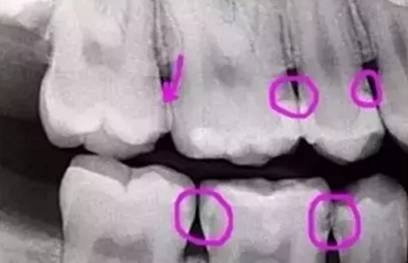

下图圈出来的地方,或多或少都有点龋齿。但是,有些你并不能看见。这些龋齿还浅不会让你有什么感觉,顶多吃东西塞牙,和冷水敏感而已。

暗的部位说明龋齿已经非常严重了!